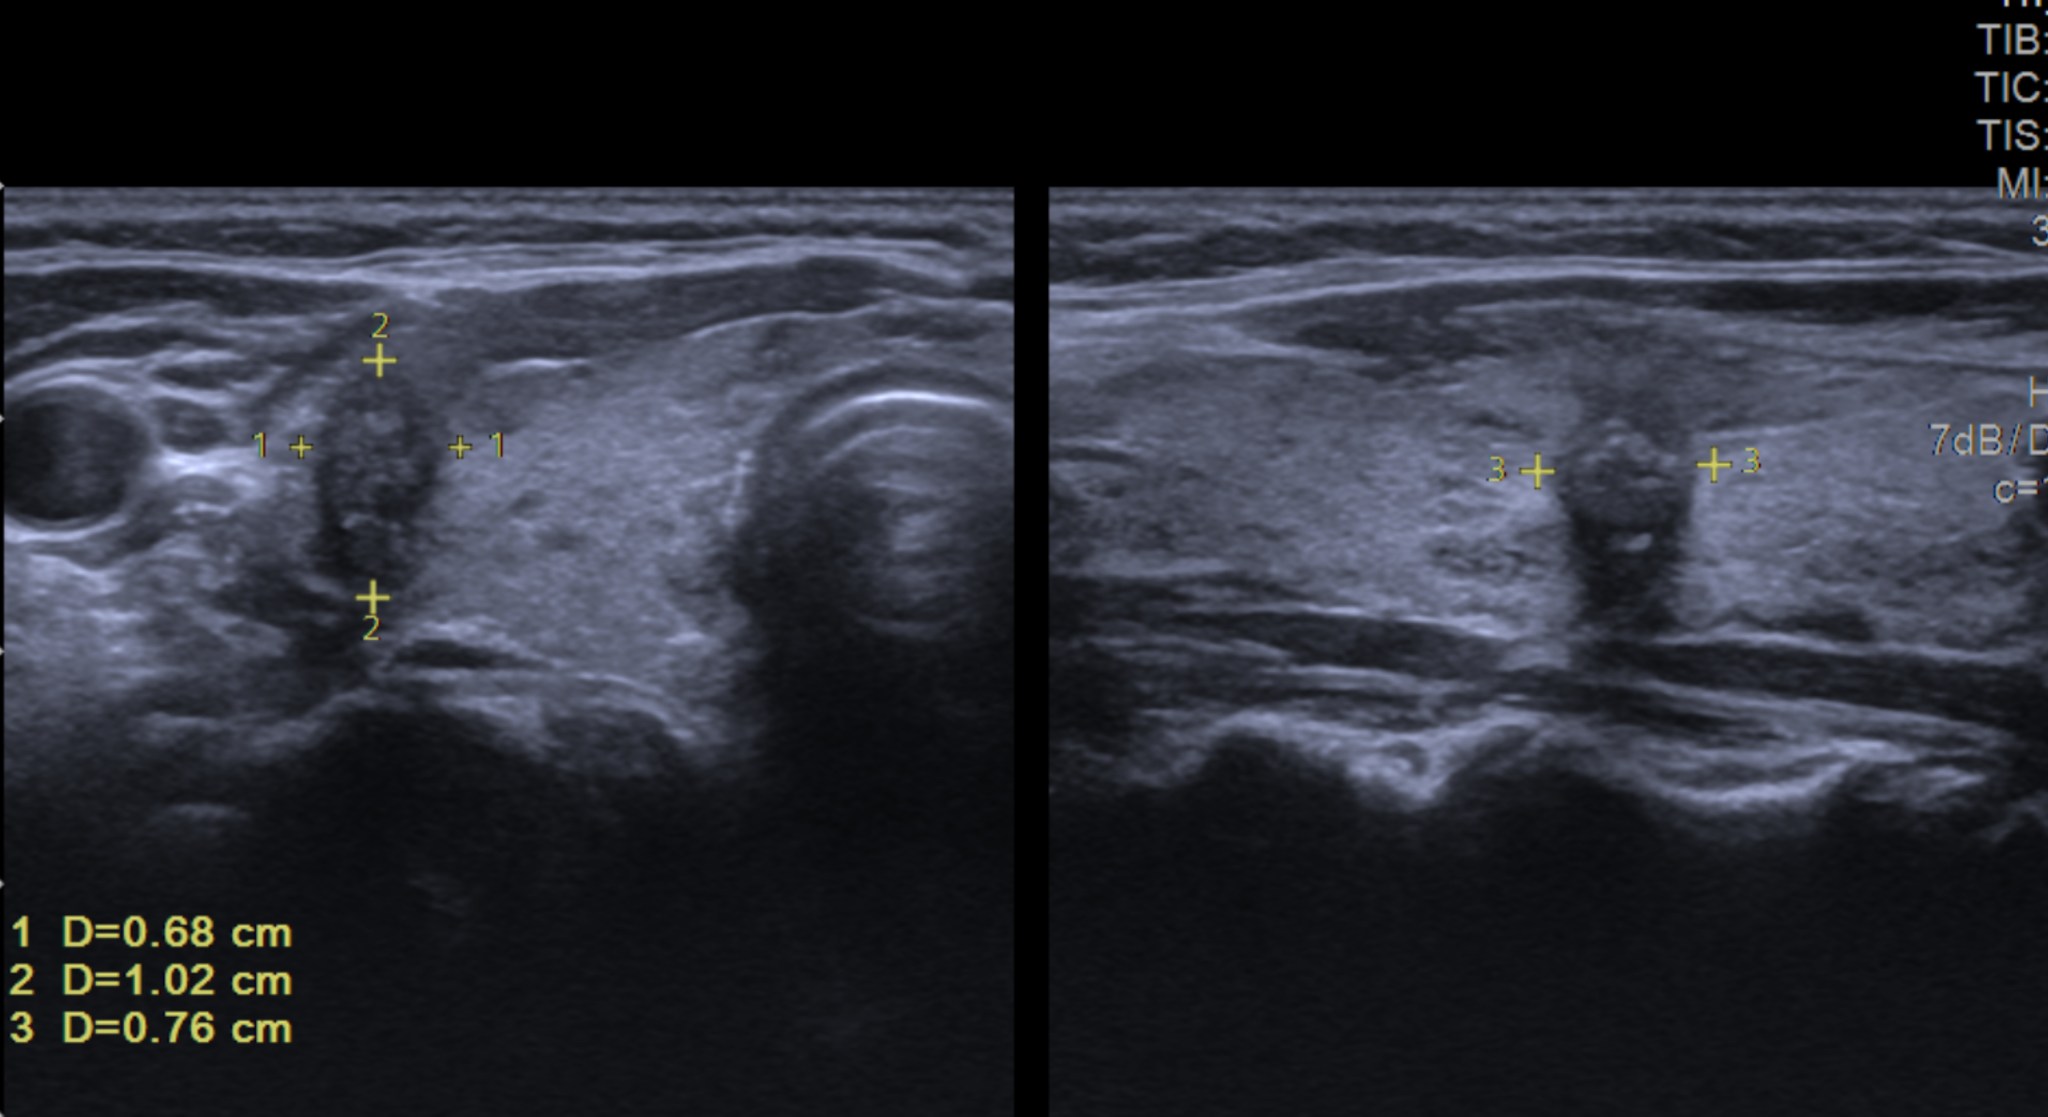

Siêu Âm Đàn Hồi: Phương Pháp Chẩn Đoán Tiên Tiến Cho Ung Thư Vú Tại Mammocare

Siêu âm đàn hồi (elastography) là một phương pháp chẩn đoán hình ảnh tiên tiến, đang được sử dụng rộng rãi tại Mammocare để đánh giá tính đàn...